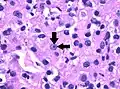

- Grade 3: Clearly visible nucleoli at magnification of 100 times

Grade 3: Arrows point at a clearly visible nucleolus.